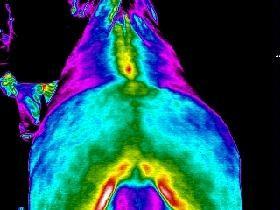

Mobile Praxis für TCVM Akupunktur (Nadel & Laser), Phytotherapie nach TCM und westlich, Mykotherapie, Lasertherapie (LLL) für Pferde und Haustiere weitere Leistungen: Blutdiagnosen, Urin & Kot Untersuchen, Untersuchungen und Behandlung bei KPU (Kryptopyrrolurie), Fell- und Haar Mineralanalysen. Orthomolekulare Medizin Eavet Metavital-Horse EquiScan- das revolutionäre Diagnoseverfahren. Endlich wissen, was dem Pferd wirklich fehlt. Schnell, zuverlässig und schonend. Mehr Infos unter www.eavet.vet Thermographie für Pferde und Hunde

Thermographie PferdKomplett-Check mit bis zu 8 Aufnahmen |

150,00 € |

Thermgraphie HundKomplett-Check mit bis zu 8 Aufnahmen |

130,00 € |

SattelkontrolleSattelkontrolle durch Thermographie |

60,00 € |